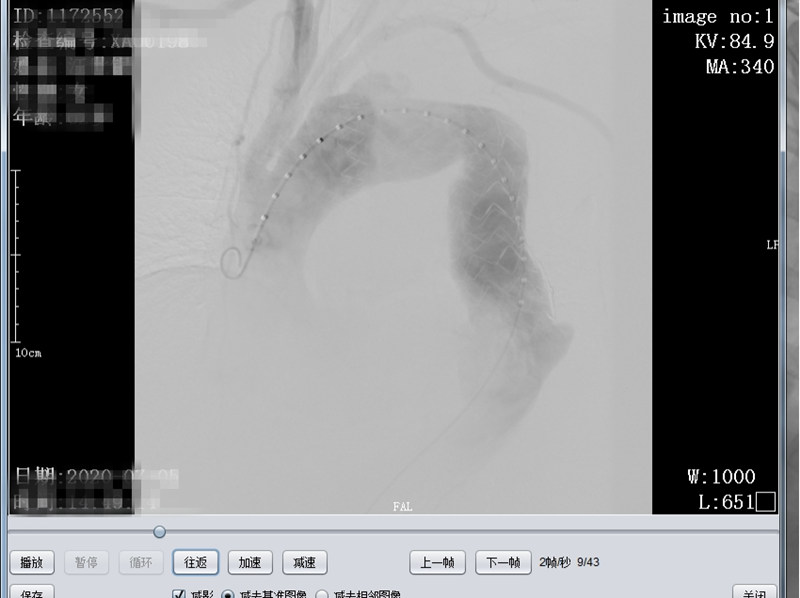

术中造影明确真假腔位置及与周围大血管关系

术后造影假腔消失,左锁骨下动脉显示良好,支架周围未见造影剂外溢(内瘘)征象